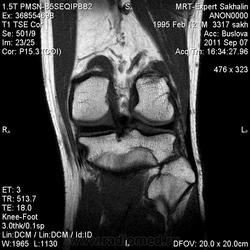

МРТ коленного сустава.Остеома малоберцовой кости?

Сегодня был молодой человек без направления.Принес диск КТ-исследования  коленных суставов от 2010 года.Заинтересовала малоберцовая кость.

И клиника какая? Болезненность есть? По МР-сигналу если все вышеизложенное исключается больше данных за остеохондрому, (экзофитное расположение, сигнальные характеристики костного мозга)

Не знаю-может быть и вариант строения.Но правая малоберцовая кость не изменена.Кортикальный слой не нарушен.Как мне показалось-по сравнению с КТ-исследованием без динамики.

Склоняюсь к остеохондроме.

КХЭ с неоартрозом с большеберцевой костью и деф. артрозом в этом суставе...  Но экзостозы обычно множественные...

Нет, Анатолий Владимирович, экзостозы чаще солитарные. По МКБ "остеохондрома" и "множественные костно-хрящевые экзостозы" вообще разные нозологии.

Касательно данного случая. Думаю - остеохондрома.

Тем не менее, настоятельно призываю коллег придерживаться общепринятых (и у нас, и у буржуев) стандартов диагностики заболеваний костей. Согласно которым, основным методом диагностики является обычная рентгенография. КТ- очень полезный дополнительный метод. МРТ - дополнительный метод, имеющий более узкие показания. МР-семиотика опухолей костей в достаточной мере не разработана, поэтому в костной патологии не стоит делать заключения только по МРТ, без данных рентгенографии или КТ